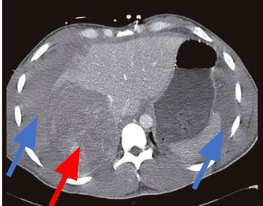

HEMANGIOMA HEPATICO

eparem que é uma lesão hipoatenuante que apresenta um realce na sua periferia, o qual é descontínuo, globuliforme e vai enchendo a lesão progressivamente nas fases mais tardias.